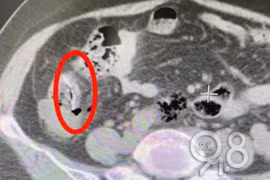

Sau khi khám, bác sĩ phát hiện bạch cầu của người phụ nữ tăng quá mức nghiêm trọng, đây là dấu hiệu cảnh báo bệnh viêm phúc mạc, trong ruột non có những mảnh dị vật, nghi là xương cá mà cô đã nuốt phải vài ngày trước.

Mảnh xương cá đi từ miệng xuống đường tiêu hóa, bằng cách nào đó đã xuyên thành ruột, tạo thành khối áp-xe dính chặt vào bàng quang, khiến bệnh nhân suýt chết.